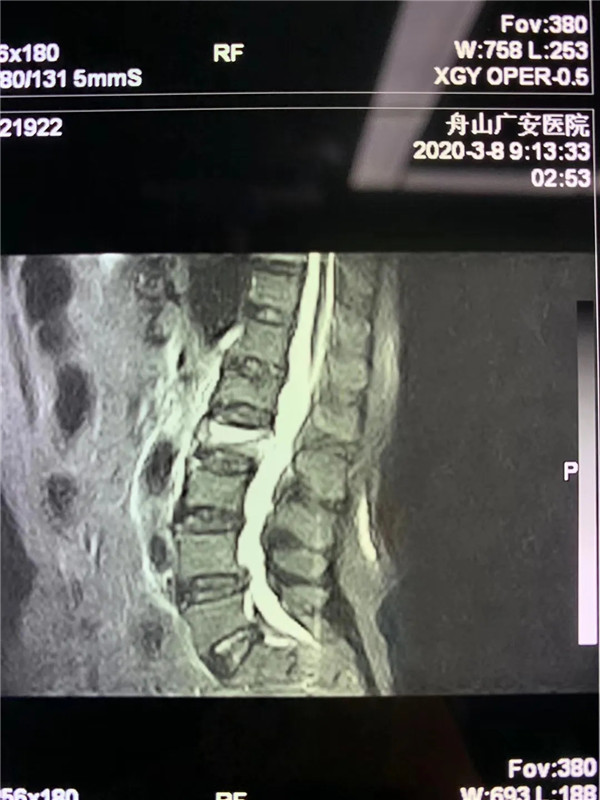

經(jīng)過仔細問診和查體后,初步診斷曹阿姨是椎體壓縮骨折了,在完善胸腰椎的MRI線檢查后,也證實了推斷。在與曹阿姨及家屬充分溝通后,戈才華主任為曹阿姨實施了微創(chuàng)手術(shù),很快為其緩解了疼痛。

(MRI顯示椎體壓縮性骨折)